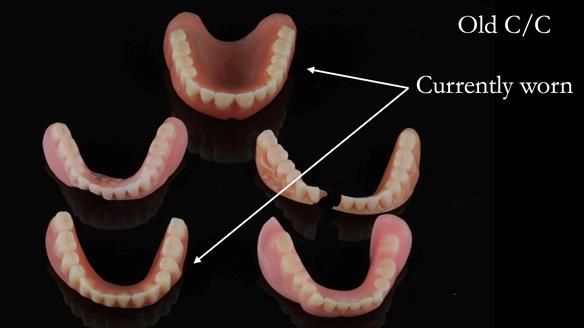

Dennis had been provided with MANY sets of dentures by both dentists and clinical dental technicians (denturist). None had proven satisfactory. The latest set had been reinforced with metal because of breakages.

Following consultation, the patient chose to have replacement upper and lower conventional metal reinforced dentures made (professional fee £7,978 GBP). Metal reinforcement was given because of a history of breaking dentures. The lower denture was designed to allow conversion to an implant supported over denture if required (additional fee £12,542 GBP).